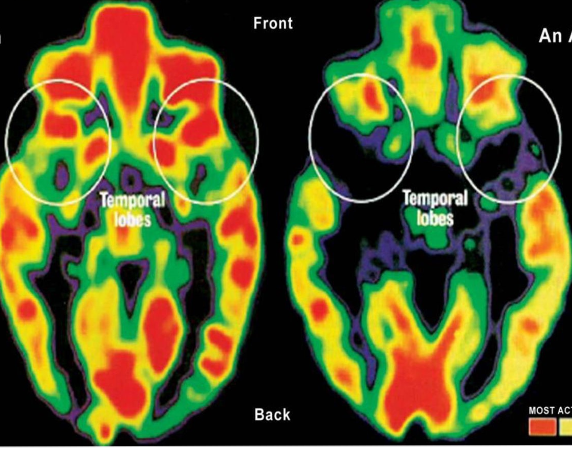

Hình (bên trái) PET scan não bộ một trẻ khỏe mạnh: những vùng mầu đỏ là vùng hoạt động mạnh; những vùng xanh và đen là vùng ít hoạt động. Lúc mới sanh, chỉ có vùng cuống não (ở giữa) là hoạt động đầy đủ; ở những vùng như thùy thái dương (temporal lobes (ở trên)) những kinh nghiệm tuổi thơ đưa đến sự hình thành những mạch nối kết.

Hình (bên phải) PET scan não bộ một trẻ thơ bị ngược đãi (trẻ mồ côi người Romanian) bị bỏ trong viện mồ côi ít ngày sau khi sanh: cho thấy tác dụng của sự thiếu thốn cùng cực lên óc. Thùy thái dương (ở trên) là nơi điểu chỉnh cảm xúc và tiếp nhận từ các giác quan gần như hoàn toàn yên lặng. Những trẻ em này có những vấn đề về cảm tính và nhận thức.